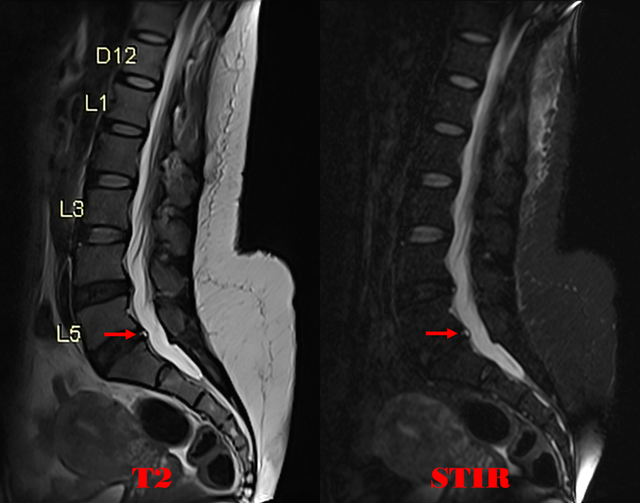

● HIZ:即High intensity zone,腰椎椎间盘高信号区,是诊断椎间盘源性腰痛的重要MRI征象,其在急性重度下腰痛患者MRI中更明显。

● HIZ经典征象是指腰椎间盘后缘局限性高信号区,由Aprill等首次在0.6T MRI上发现,形态多为小圆形。部分学者将其细分为五种形态,即圆点型、垂直型、水平裂隙型、斜型、膨大型。

● 可发生于纤维环前缘或后缘,均位于外侧近边缘处。

● 代表椎间盘纤维环的裂隙/撕裂,血管化肉芽组织向撕裂处的生长。

● 相关文献认为HIZ好发于L4-5和L5-S1,所占比例高达 70%~90%。上腰段发生率较小,为10%~30%。L4-5和L5-S1 发生几率相似。研究发现 HIZ 多位于椎间隙下部,其次为中部,上部最少见。

● 影像表现:

◆ MRI T2矢状位及T2横断位可见椎间盘前缘或后缘局限性高信号区。

在L5-S1椎间盘的轴位图像上,纤维环中心可见T2高信号区。